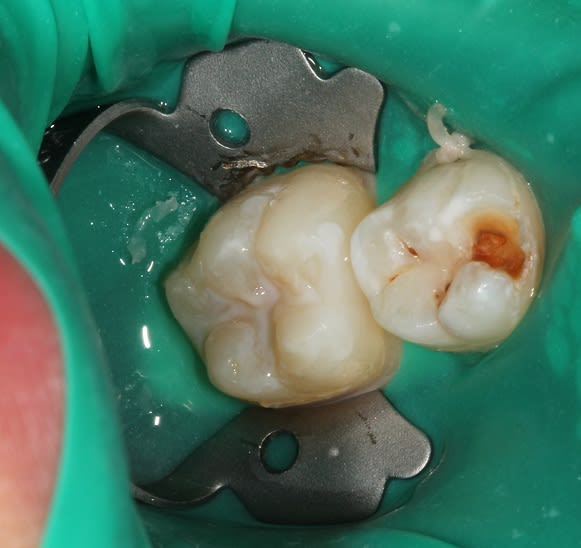

21-12-2011_11-07-33_wbkjbg.jpg

Voir le message contenant cette image